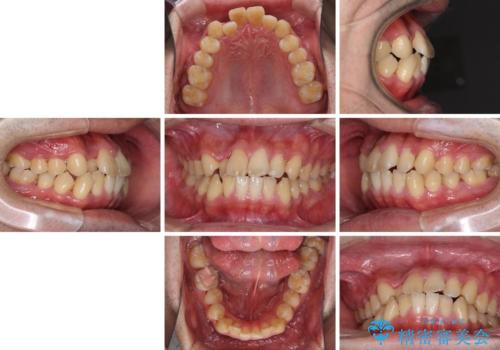

前歯のクロスバイトを改善 インビザラインによる矯正治療

- 前歯のクロスバイトを気にして来院された患者様です。

デコボコやクロスバイトが散見されたため、IPR(歯と歯の間を削る)によってスペースを獲得できるように設計し、インビザラインにより治療を行うこととしました。

上顎側切歯(上の真ん中から2番目の歯)が舌側転位している場合、インビザラインでは仕上げきれない可能性があり、更には無理して動かそうとすると歯髄壊死を起こすリスクが高いと言われています。

安全に治療を行う対策として、インビザラインで歯列を移動する前に、上顎前歯をワイヤー矯正で整え、その後上下歯列をインビザラインにて矯正治療を行うプランを提案しています。

今回は、ワイヤー装置を併用することなく治療を行い、トラブルなく、満足のいく歯列に整えることができました。